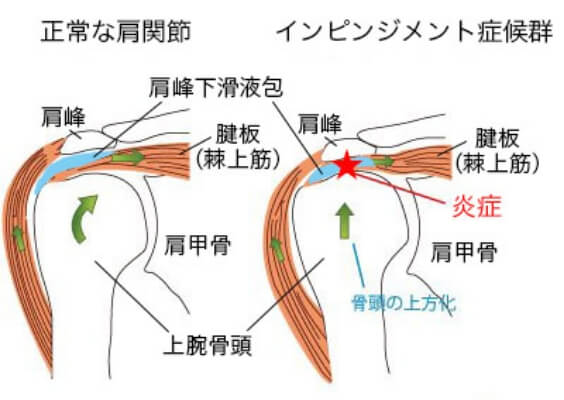

1.インピンジメント症候群

野球肩の原因の中でも多いのがインピンジメント症候群です。肩を使うたびに、肩峰や靱帯に上腕骨頭が衝突することにより、腱板※がはさまれ、肩峰下滑液包に炎症を起こし、肩が痛みます。野球の投球動作の他、ラケット競技など、腕を上に振り上げる動作を繰り返すスポーツでも発症します。

肩を上げていくとき、ある角度(70〜120°あたり)で痛みや引っかかりを感じ、それ以上肩を挙上できなくなリます。このような症状がインピンジメント症候群の特徴になります。